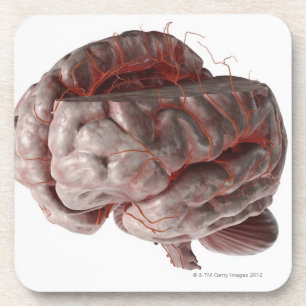

Impressão Em Tela Imagem conceptual do cérebro humano 6

PreçoR$ 589,00